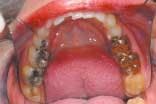

The upper and lower occlusal shots, as well as the four individual quadrants, are captured next. The four individual quadrant shots are the most powerful of the series. These are the shots where a patient can see old restorations, wear facets, recurrent decay, poor contour, etc. It is with the quadrant shot that the patient asks for dentistry. The doctor does not need to sell it!